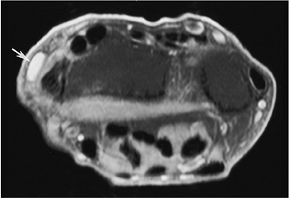

FIGURE 9-56 MR images in patients with ulnar lunate abutment syndrome. (A) T1-weighted image shows low signal intensity in the lunate and adjacent triquetrum. (B) Gradient echo coronal shows displacement of the radial aspect of the triangular fibrocartilage (open arrow) and a peripheral tear (black arrow).